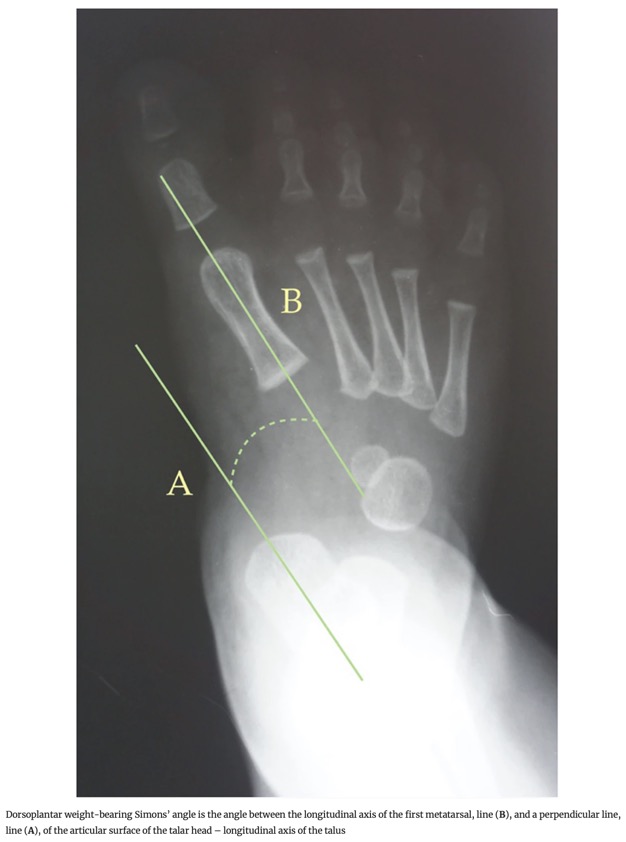

- 3. Angle de Simons : Angle entre l'axe longitudinal du premier métatarsien et une ligne perpendiculaire à la surface articulaire de la tête du talus.